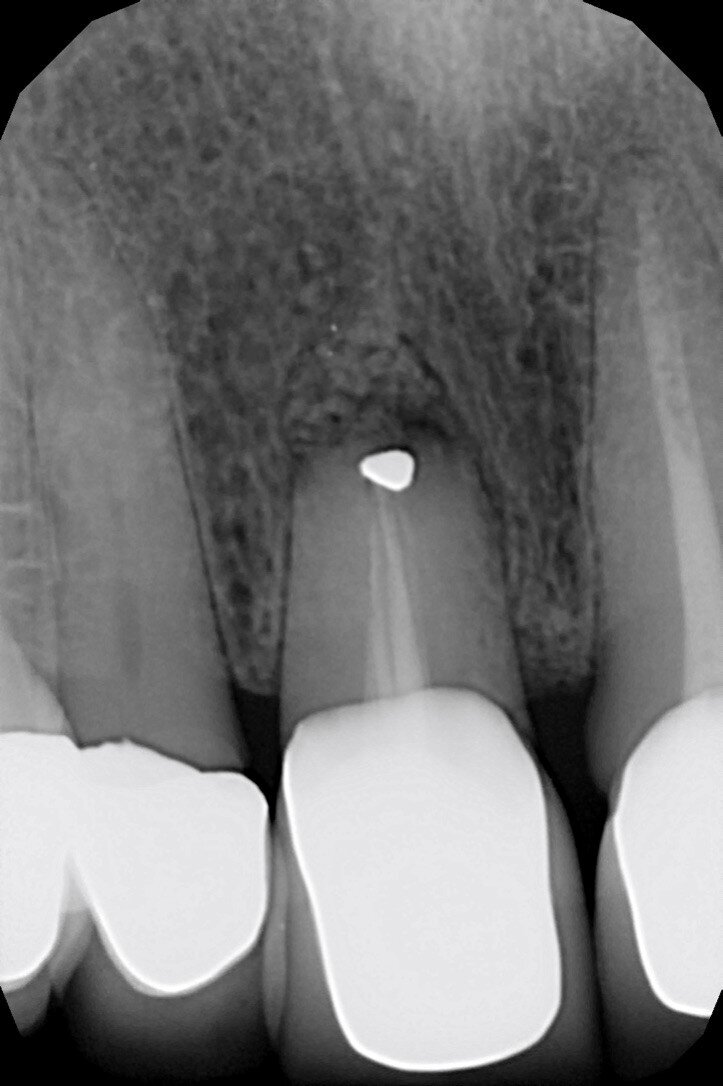

Le radiografie del caso completato nell’inizio del 2010 (Fig. 4) evidenziano la precisione del lavoro che è poi stato mantenuto nel corso degli anni. L’incisivo centrale destro 11 era stato trattato con apicectomia in passato ed era l’unico dente non vitale della riabilitazione. La paziente era seguita dal protesista che aveva portato a termine il caso. Nel 2021 la signora si è ripresentata con sintomatologia sul dente 21. Il lavoro eseguito nel 2010 era ancora in buone condizioni fatta eccezione per 11-12 ove 12 presentava una recessione gengivale con esposizione del collarino della cappetta galvanica che supportava la corona in ceramica e 11 presentava una piccola fistola nella sua porzione vestibolo distale (Figg. 5-7). La diagnosi era abbastanza semplice, l’11 aveva una frattura verticale e una prognosi infausta.